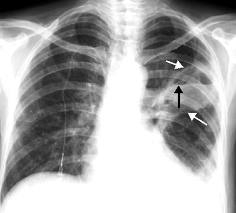

Абсцесс легкого – ограниченный гнойный процесс в ткани легкого, вызванный проникновением бактерий, грибов, простейших при пневмонии, инфекции других органов, при аспирации инородных тел, при распаде опухоли в легких и т.д., в результате чего в легких образуются полости, заполненные гнойным содержимым.

ДИАГНОСТИКА

Диагноз ставится на основании анамнеза и клинической картины заболевания. Инструментальные исследования подтверждают диагноз. При бронхоскопии возможен забор материала для бактериологического и цитологического  исследования.

Медицинские процедуры, проводимые при заболевании абсцесс легкого: Рентген, Компьютерная томография, Бронхоскопия, Пункционная биопсия, Клинический анализ крови, Посев мокроты с расшир. спект. а/б